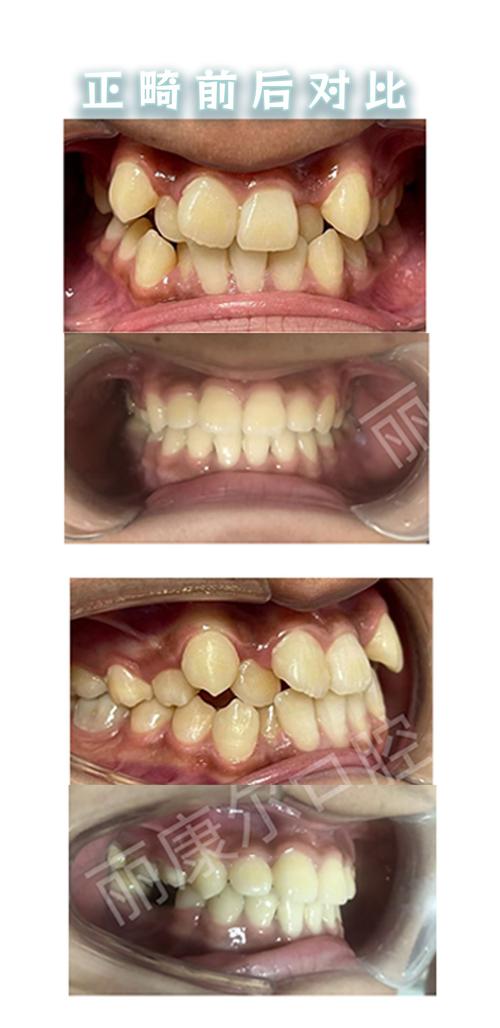

通过视频向患者展示治疗前后变化(如“凸面型”变为直面型、露龈笑的改善),让患者直观理解治疗目标,增强配合度;同时解释可能出现的暂时性变化(如治疗初期面部肿胀),减少焦虑。

- 牙合像视频:包括正面牙合(上下牙咬合时的暴露情况)、侧面牙合(磨牙咬合关系及覆牙合覆盖程度),动态展示牙齿排列、牙弓形态及咬合接触点。